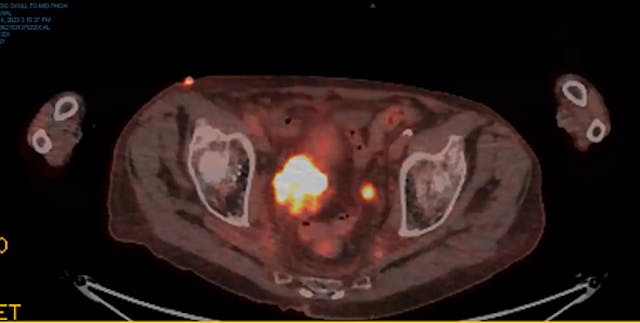

metastatic prostate cancer, back pain, retroperitoneal adenopathy, Degarelix, Xtandi, Taxotere, Docetaxel, Prednisone, side effects, PSMA PET CT, avid expression, left sacral ala, castration resistant, ADT, tumor genomic profile, immunotherapy, homologous repair defect, urinary symptom palliation...

PSA, PSMA, PET scan, regional nodes, external iliac artery, right and left obturator, left perirectal, rib trauma, Zytiga, Lupron, bladder preservation, rectum, 60 Gy, toxicity, SIB, abdominal GI cramping, diarrhea, urology, ADT, prostate, salvage brachytherapy, SBRT, ASCENDE-RT trial, brachy boo...